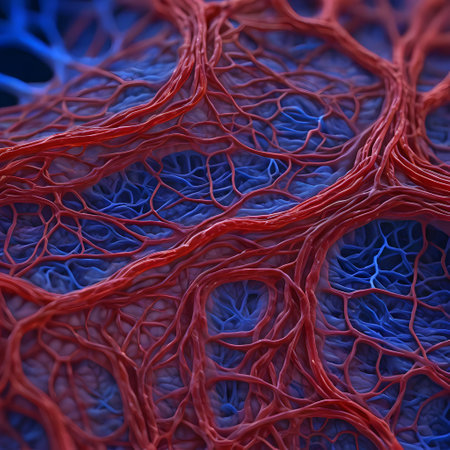

Macro view of human blood vessel network with red and blue tones showing capillaries and vein structure, ideal for illustrating medical anatomy and biology research.

Detailed visuals showcase the complex network of blood vessels in human anatomy.

Vessel flow texture in red and blue lighting showing microscopic circulation system pattern symbolizing human biology, anatomy, and healthcare science visualization.